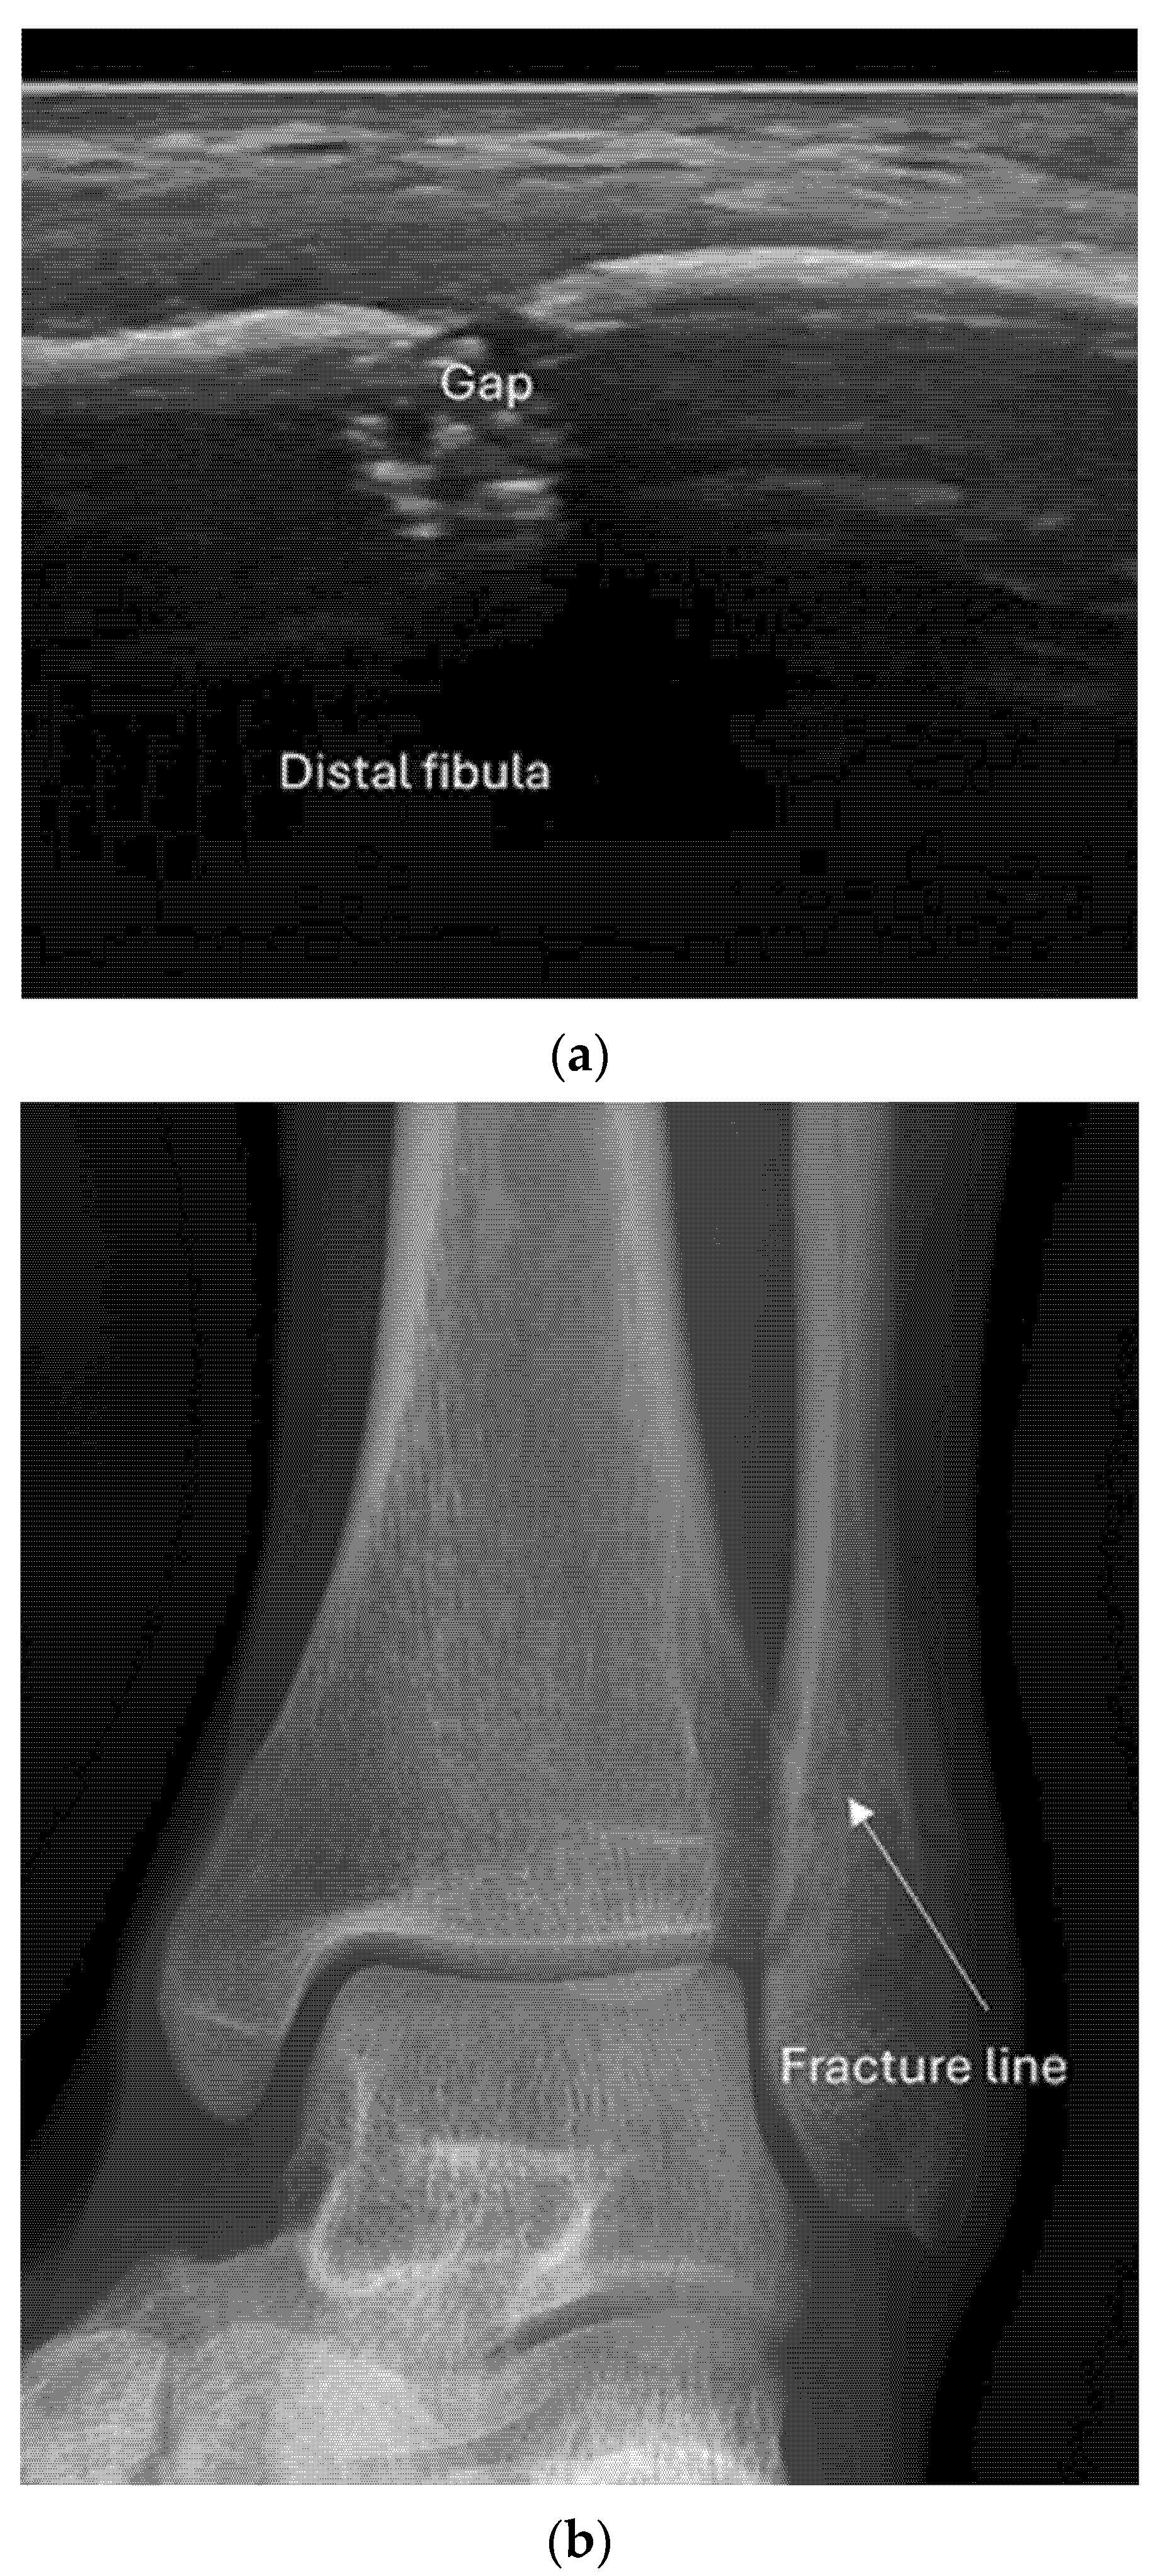

4.2. Sonoanatomy of Fractures [Figure 5, Figure 6, Figure 7 and Figure 8]

- Irregularity, interruption, or gaps in the cortical line: the cortical bone normally appears as a continuous, bright echogenic line, which is interrupted or irregular in the presence of a fracture.

- Reverberation artifacts within or adjacent to the fracture gap (also known as the “chimney sign”): these repetitive echoes are caused by ultrasound waves reflecting off the fracture surfaces.

- Dislocation: misalignment of bone fragments, visible as separation or shift from their normal anatomical position.

- Example: Stress Fracture